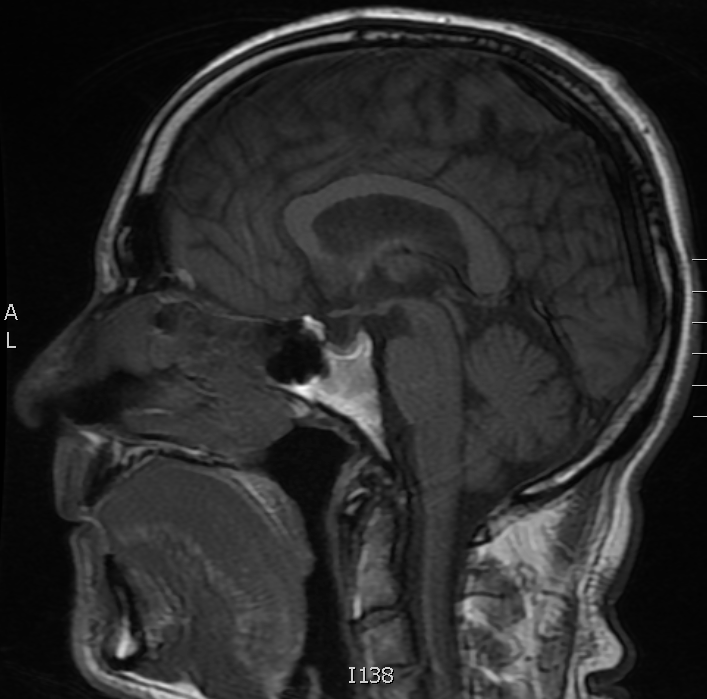

OK – time to review, can you tell which sequence is T1W and which is T2W? Look at the two saggital MRI’s below and decide which is which, then scroll down for the answer.

Image A

Image B

Image A is a T1W study – the corpus callosum, a large white matter tract, is bright. Image B is a T2W FLAIR study, the corpus callosum is grey. Notice that the fat is bright on both.